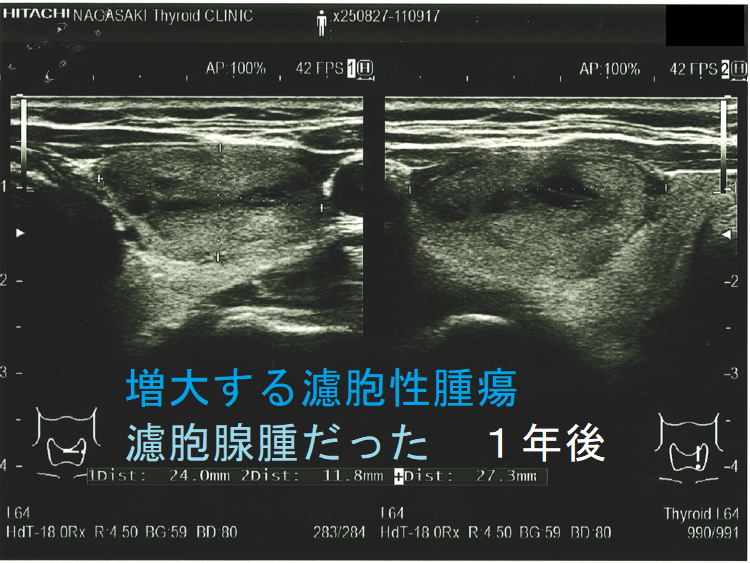

増大する濾胞性腫瘍 濾胞腺腫だった

ある意味、腫瘍の増大速度程、悪性の可能性を疑わせる所見は他にありません。急激な速度で大きくなる濾胞性腫瘍は、異常な速度で細胞増殖がおこっています。それは高い確率で甲状腺濾胞癌であると考えざる得ません。(サイズ増大で甲状腺濾胞癌と診断)